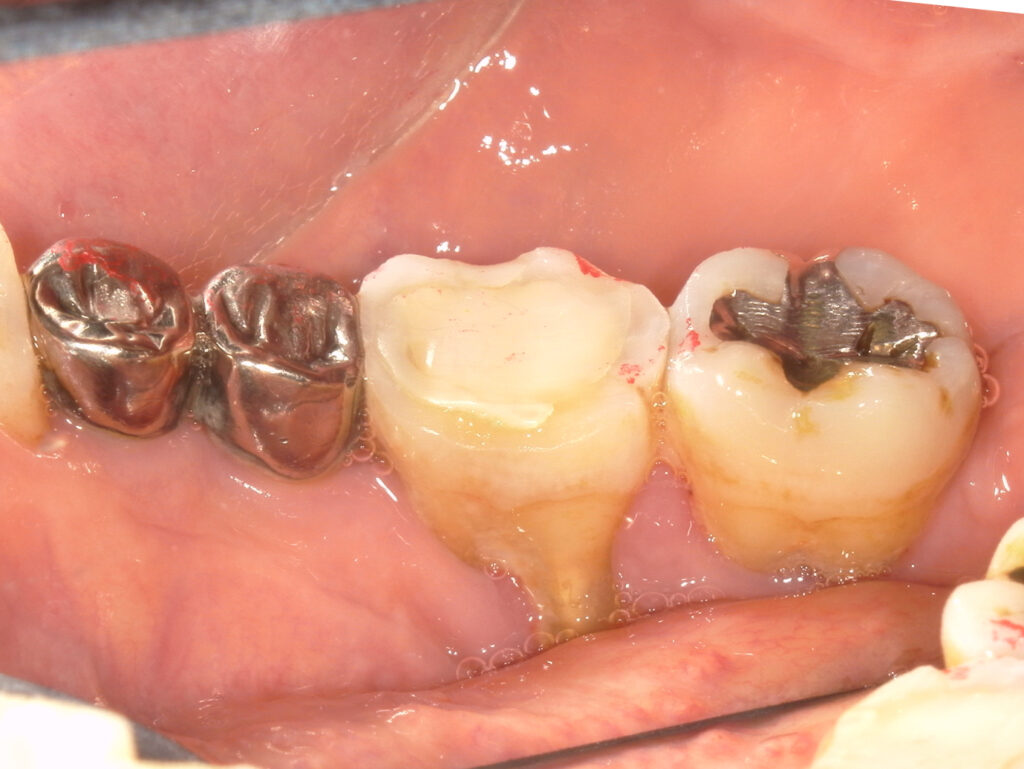

●治療内容

右下5,7 ブルーラジカル処置

ブルーラジカルP-01は歯ぐきを切らずに、光の力で歯周病菌へ直接アプローチする非外科的な治療法です。

軽度から重度まで対応可能。

これまで治療の選択肢が限られていた重度のケースでも、ひとつの選択肢となる場合があります。

ただし、進行度によっては再生療法など他の治療法がより適している場合もあります。

検査結果をもとに、最適な方法をご提案します。